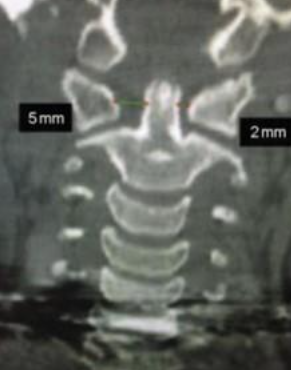

Qual é o exame radiográfico chave para a Síndrome de Grisel?

RX Transoral, que avalia a presença de assimetria no espaço entre o odontóide e as massas laterais de C1.

Como a Tomografia Computadorizada é usada na Síndrome de Grisel?

Fornece informações detalhadas sobre a posição das vértebras C1 e C2.

Quais são os sinais radiográficos importantes na Síndrome de Grisel?

Assimetria no espaço entre o odontóide e as massas laterais de C1 e o Wink Sign.